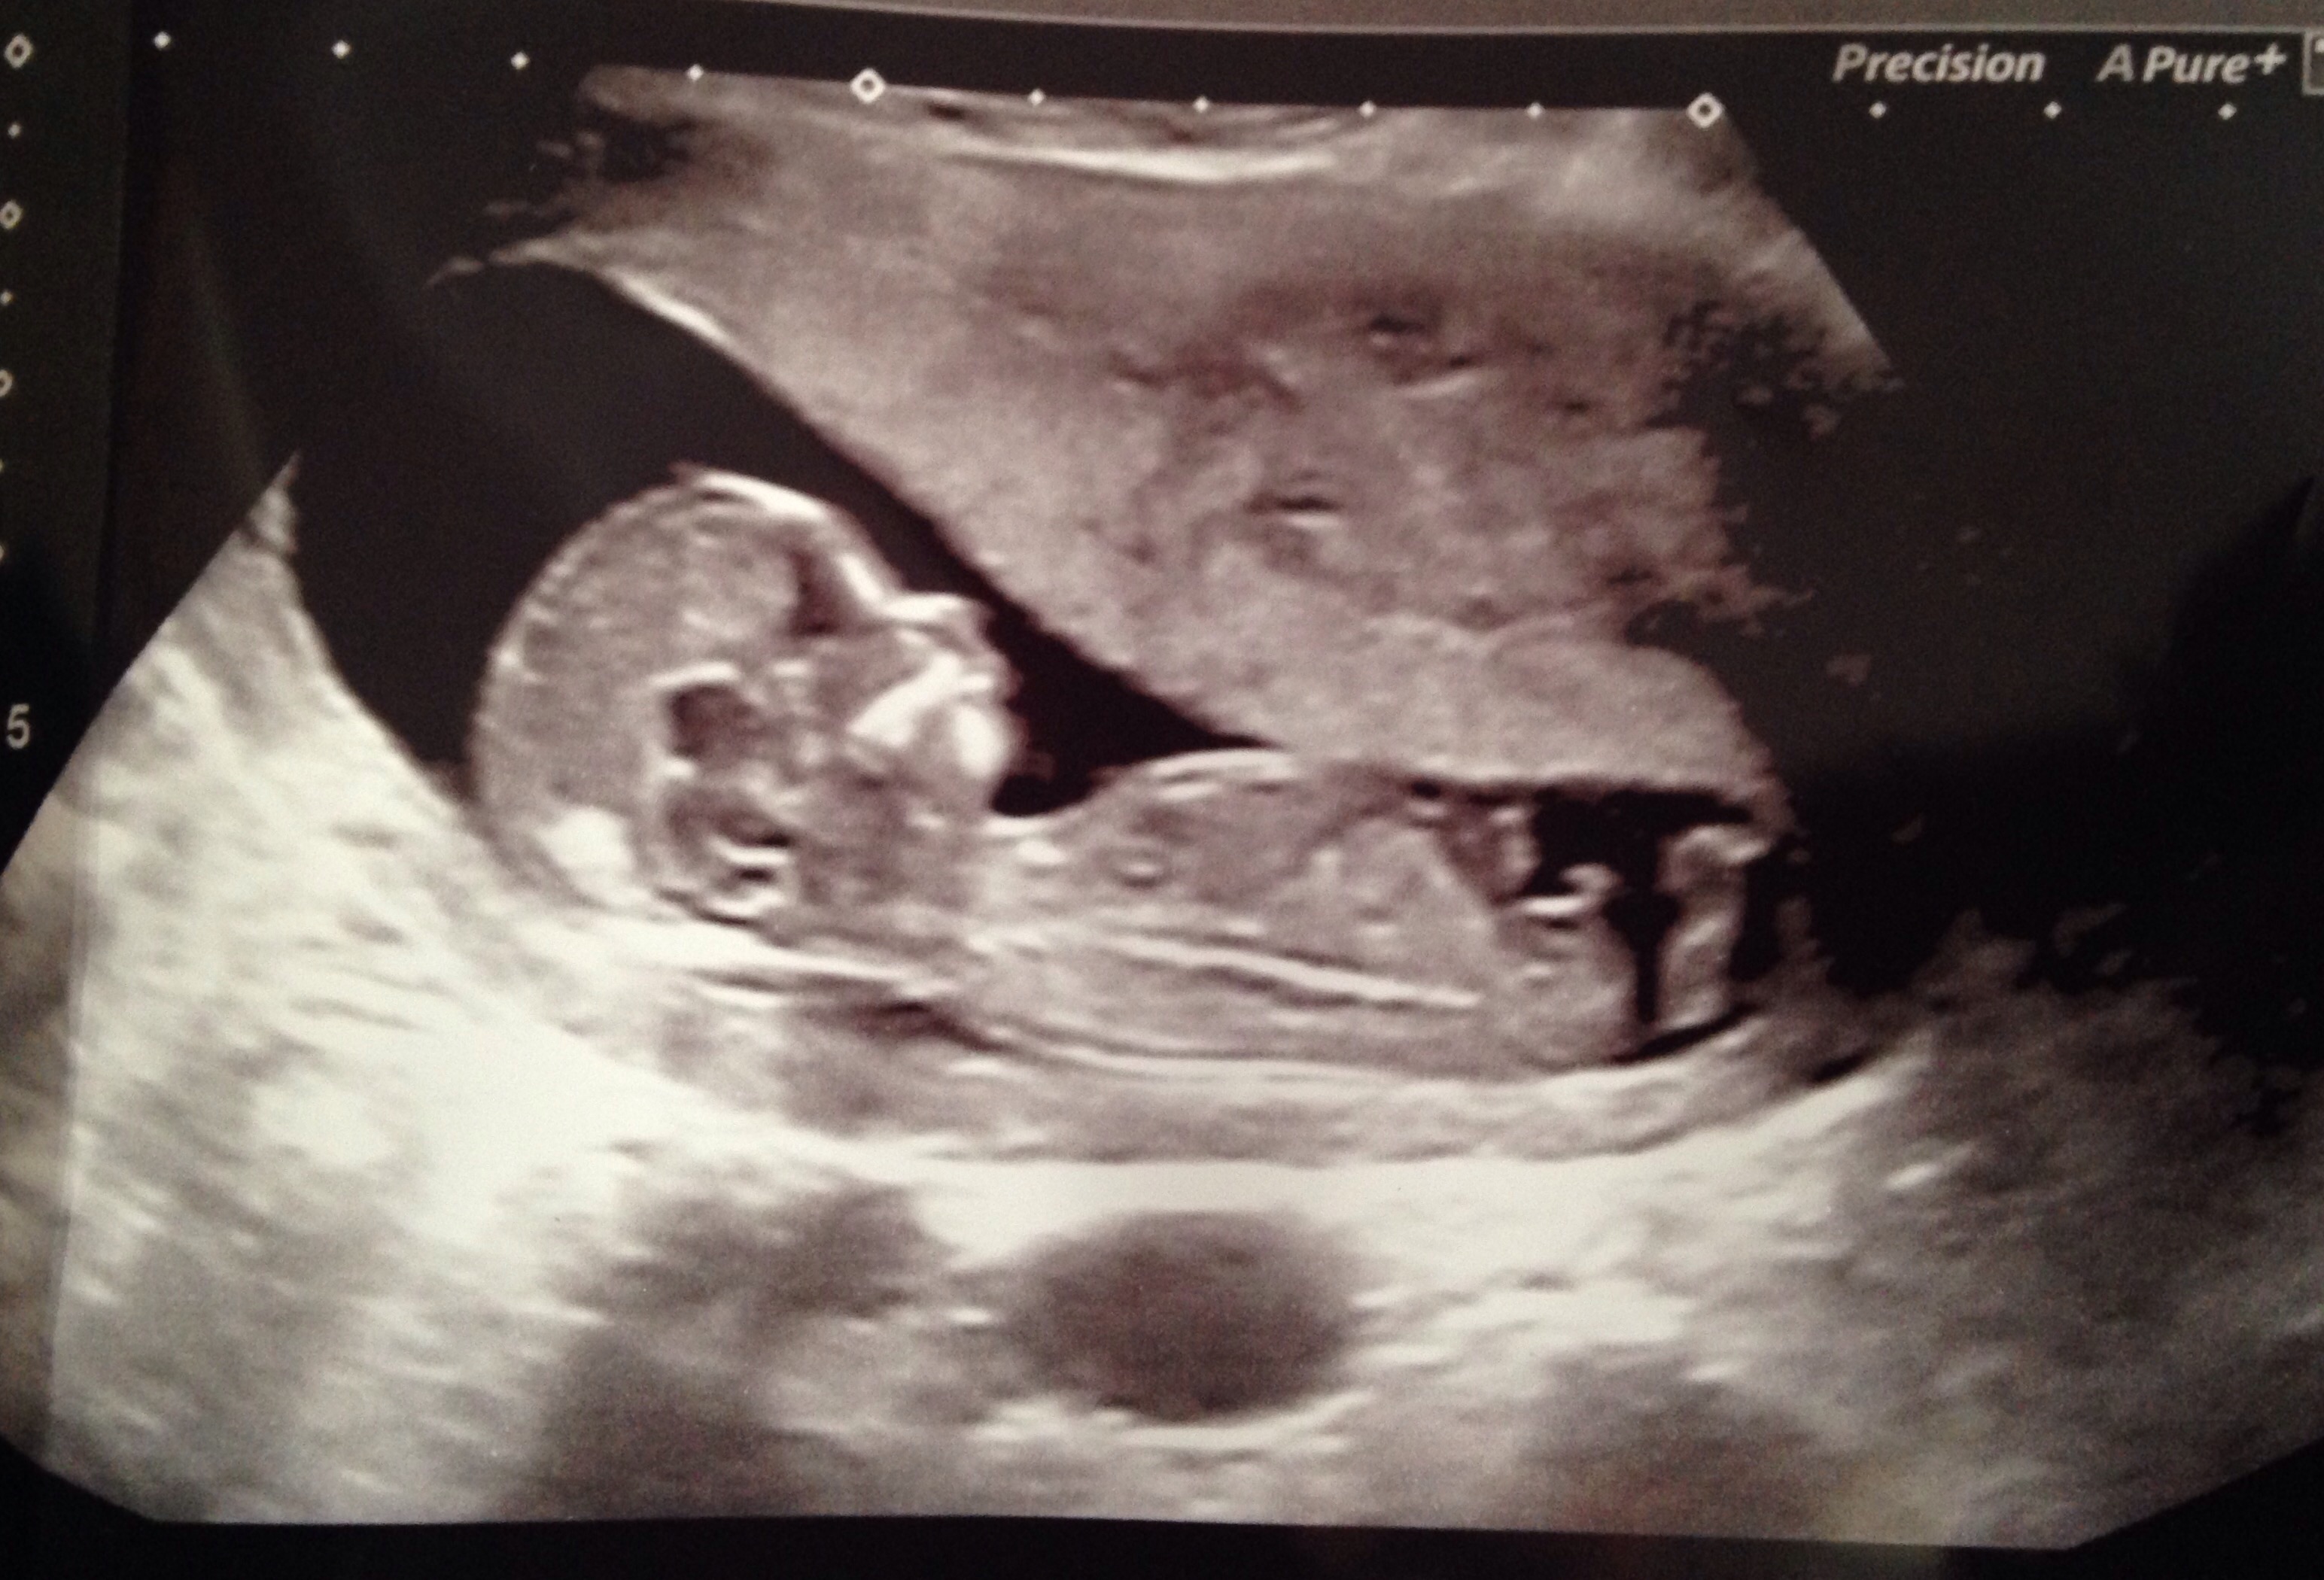

Want as many opinions as possible... Confused with this nub.. It's paralel but has a bump!!!

Definitely boy. That is what is referred to as the stacked nub!

Nahri..... What does a stacked nub mean please? I'm confused cos it's completely parallel like a girl but got a curve on the end! Wracking my brain lol! Thank you!

That bump on the end usually indicates boy.

But the line thing is flat and parallel which indicates a girl Doesn't it? It's not at all slanted upwards?? But a bump indicates a boy lol!